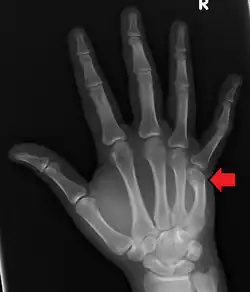

A healed fracture of the neck of the 5th metacarpal

Prognosis for these fractures is generally good, with total healing time not exceeding 12 weeks. The first two weeks will show significantly reduced overall swelling, with improvement in clenching ability showing up first. Ability to extend the fingers in all directions appears to improve more slowly. Hard casts are rarely required, and soft casts or splints can be removed for brief periods of time to allow for cleaning and drying the skin underneath the splint.[11] Pain from injury varies person to person as with most injuries. Depending on the individual a course of over the counter or narcotic pain medication will suffice. Muscle atrophy of 5 to 15 percent may be expected, with a rehabilitation period of approximately 4 months given adequate therapy. In the mildest of cases, full rehabilitation status can be achieved within 3 to 4 months.